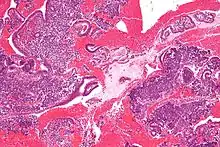

Display of small round blue cells characteristic of desmoplastic small round cell tumour.

In histopathology, a small-blue-round-cell tumour (abbreviated SBRCT), also known as a small-round-blue-cell tumor (SRBCT) or a small-round-cell tumour (SRCT), is any one of a group of malignant neoplasms that have a characteristic appearance under the microscope, i.e. consisting of small round cells that stain blue on routine H&E stained sections.

These tumors are seen more often in children than in adults. They typically represent undifferentiated cells. The predominance of blue staining is because the cells consist predominantly of nucleus, thus they have scant cytoplasm.[1][2]